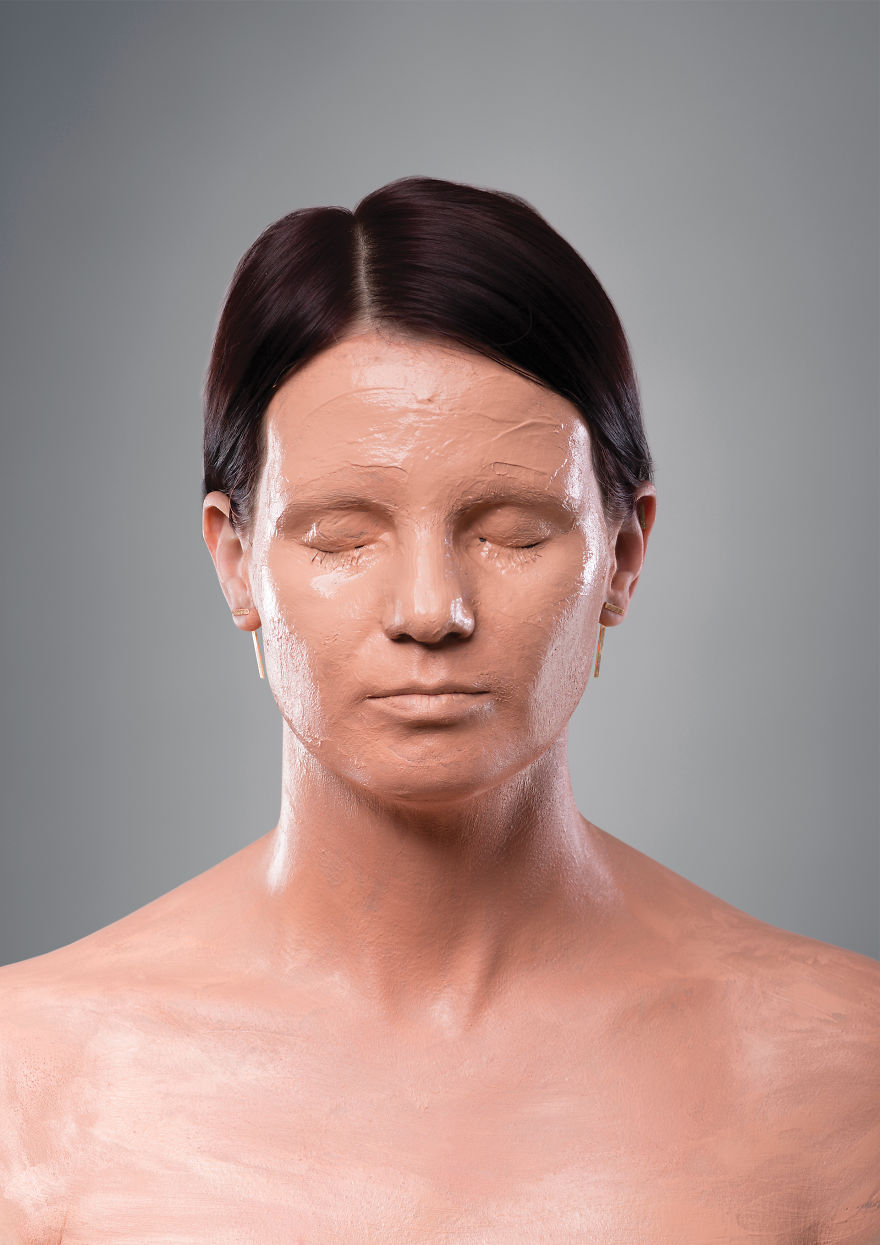

Vitiligo is a skin disorder: the skin cells cannot produce pigments as a result of which certain areas of the skin become white. The disorder affects roughly 1-3 percent of the population. As I have vitiligo as well, I chose this topic for my degree work at the Hungarian University of Fine Arts, majoring in graphic design.

The degree work introduces everyday events and situations with the help of photographs and short stories. Before starting out, I did a survey among other people suffering from vitiligo and found that similarly to my experiences they all have an ambivalent love-hate relationship with their own skin. The degree work is about how a person with vitiligo (in this particular case me) experiences the negative and positive reactions of other people.

The project was entirely concieved by me, Júlia Bodolóczki and I wrote the short stories myself as well. I asked Karolina Kárász to take photographs for my project, while the short stories are available in English as well translated by Ambrus Nagy.

As I was struggling to get out of the examination chair obviously designed for giants the doctor brought up the topic of vitiligo. I smiled and confirmed I had a natural pigment deficiency which I had already accepted as to my knowledge it still had no known cure. He nodded enthusiastically and said how great this all was, but soon after he changed his tune completely. Uncle Miki – who by the way is not the sort of person one can easily interrupt – started asking me if I knew about the superb cosmetic products available that could cover such patches of skin not just on the face but on the whole body. My affirmative answer did not seem to distract him one bit as he continued to recommend the products suggesting my ugly patches would all be covered up nicely if I used them. At this point we entered into a minor argument; I explained how I’m quite happy with my patches, an idea he did not seem to believe for some reason. The situation started to become genuinely uncomfortable. I was afraid he’ll soon tie me down and apply some make up as patches like mine in his idea should never ever be seen. In the end I fortunately managed to convince him that I do not need any of this as I live quite happily and at peace with my patches in a rather extraordinary symbiosis. He fell silent for a moment but by the time I got my coat on his lips started moving again. Although I half-expected to hear the simple „Get well, goodbye” routine uncle Miki reignited the topic and once again advised me to use one of the aforementioned cosmetic products as I can’t ever know when I’m going to appear on TV or when a date is going to fall in my lap out of the blue.

My enthusiasm going in the doctor’s office had turned to complete dismay by the time I finally left. I felt uneasy on the street and this time not because of the prioral dermatitis on my face but because of my patchy skin.

As a guy who has Vitiligo and it started in my late teens and now I'm in my late 40's, I used to try and mask/hide it but then it got to the point that it was taking so long to hide the white patches I thought "why bother" Sure people will look, stare and wonder what is wrong but it is human nature, we all look and wonder about things that are different.